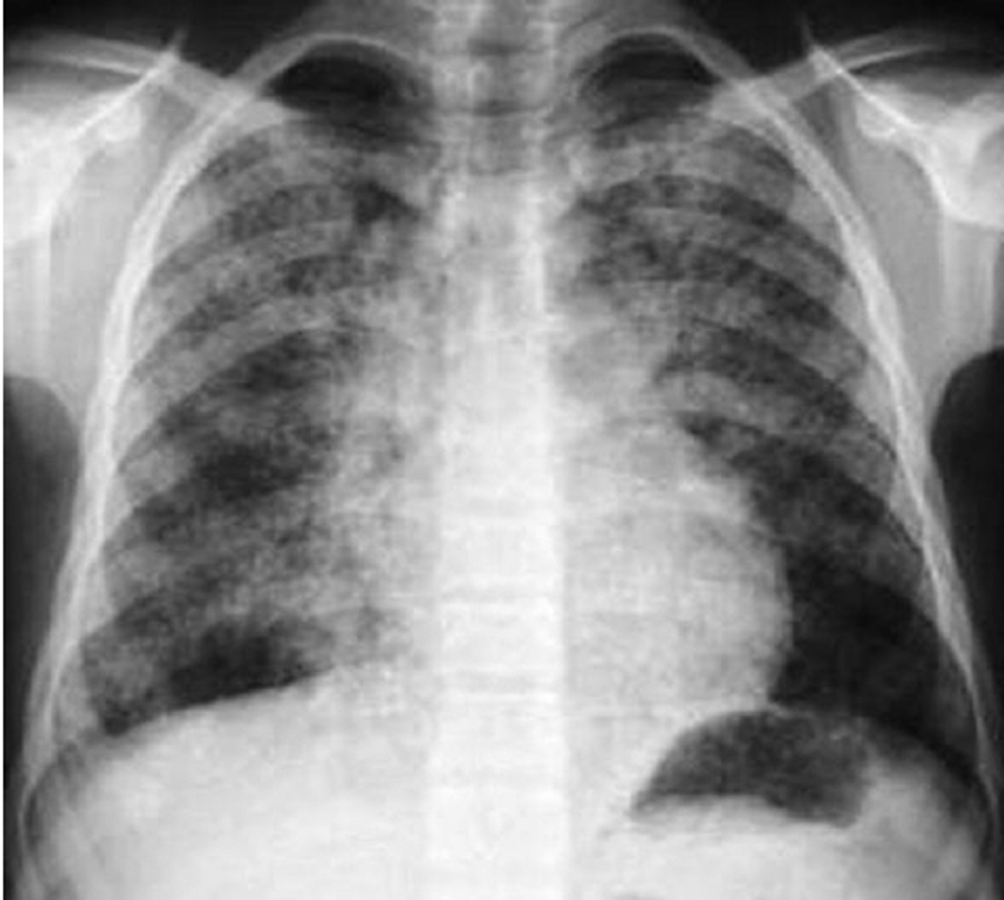

Normal CXR (PA & Lateral)